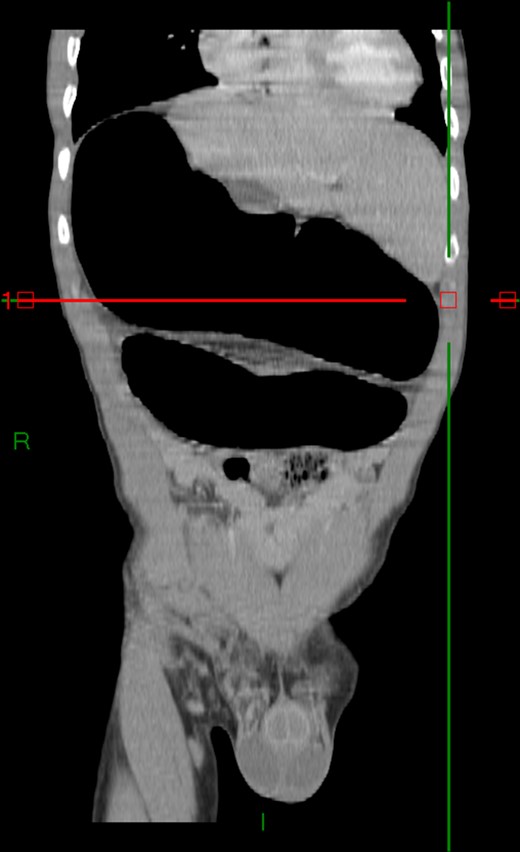

Case 2: A 92-year-old women, without previous abdominal surgery or history of abdominal trauma or peritoneal infections was admitted to the emergency department with generalized abdominal pain. Physical exam revealed markedly distended abdomen with generalized abdominal pain with tenderness. Laboratory investigation on admission: white cell count of 30.200/mm3 with 84.7% neutrophils, protein C reactive of 13.6 mg/dL and lactates of 2.17 mmol/l. Abdominal X-ray showed a marked colonic enlargement. Abdominal-pelvic CT identified a colonic volvulus associated with a transmesocolic hernia with transmural necrosis of the colon sigmoid (Figs 2 and 3). The patient was proposed to laparotomy during which a volvulus of colon sigmoid with transmural necrosis in a strangulated transverse transmesocolic and transomental (great omentum) hernia was identified (Figs 4 and 5). A Hartmann procedure was conducted and the patient was discharged at fifth post-operative day. At 3 months follow-up consultation, the patient remained free of complains.

Abdominal-pelvic CT—transverse plane: colonic volvulus associated with a transmesocolic hernia with transmural necrosis of the colon sigmoid.